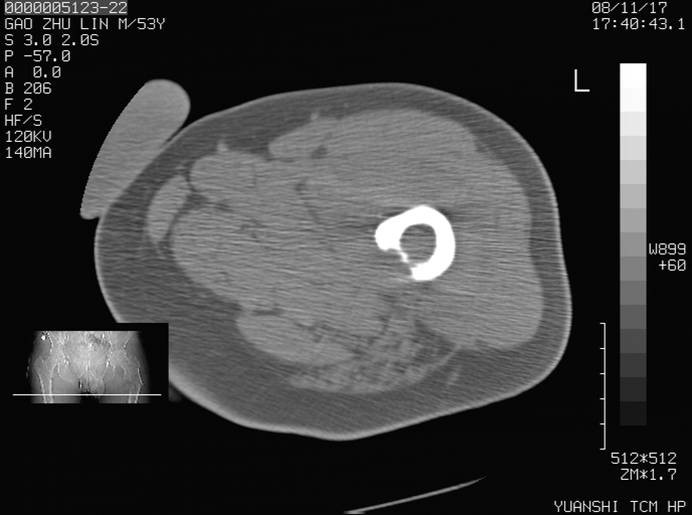

标题: CT16696:M53Y,左股骨上段骨折。 [打印本页]

标题: CT16696:M53Y,左股骨上段骨折。

左股骨上段外伤1个小时,左股骨上段疼痛。村医以腰椎间盘病变给以按摩及理疗数天。

图像不太清楚,左股骨上段外伤性骨折?病理性骨折?

左股骨上段粉碎性骨折

左股骨上段粉碎性骨折;建议上传骨窗看看是不是病理性的啊!

左股骨上段粉碎性骨折,不排除病理性骨折可能。

考虑骨肉瘤伴病理骨折

考虑:骨肉瘤伴病理骨折.

病理性骨折,考虑转移所致.